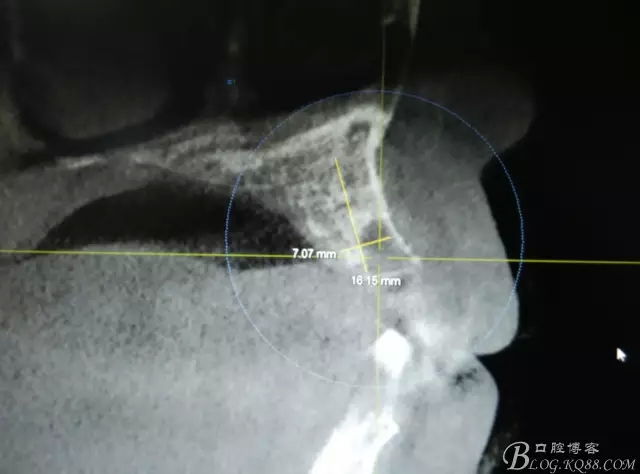

患者、楊xx、男、49歲。主訴:左側(cè)前牙拔除半年,活動義齒修復(fù)四個(gè)月,要求種植修復(fù)。??茩z查:21缺失,牙槽粘膜厚度正常。CBCT檢查:高度16mm,寬度7mm.術(shù)前簽知情同意書。

圖2.CBCT的三維成像及縱剖面、水平面影像